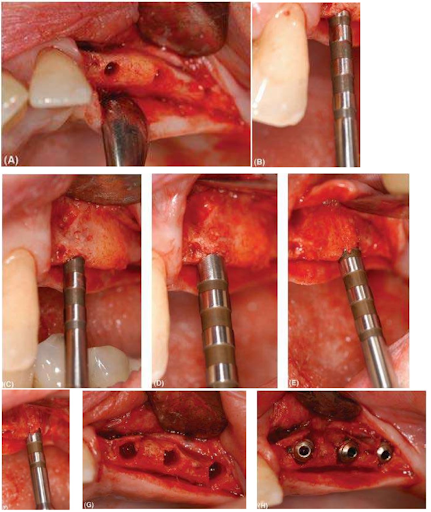

Một loạt các hình ảnh lâm sàng cho thấy sử dụng osteotome Astra Tech để nong rộng sống hàm trên ở một bệnh nhân thiếu răng bẩm sinh dẫn đến profile sống hàm rất hẹp. (A) Vùng đặt implant ban đầu được sửa soạn xuyên qua xương vỏ với mũi khoan hướng dẫn và mũi khoan xoắn 2mm. (B) Osteotome đường kính 2mm được dùng và nhẹ nhàng vặn vào và/hoặc xoay về phía chóp để mở rộng xương. (C) Các osteotome được chế tác với chiều dài implant mong muốn. Lưu ý osteotome đã tiến về phía chóp bao xa. (D) Sau đó một osteotome đường kính 2.0 / 3.2-mm được dùng ở mức mào xương theo sau là một osteotome 3,2 mm một lần nữa nhẹ nhàng tiến về phía chóp. (E) Vùng đặt implant phía xa được sửa soạn giống như vậy. Lưu ý osteotome trong vùng này có emergence về phía ngoài hơn nhờ profile xương ổ có sẵn . (F) Các osteotome đường kính 3,2 mm đã đi đến 13 mm. (G) Hoàn thành vùng khoan xương. Lưu ý xương vỏ phía ngoài 2 răng cửa đã có sự nứt nhẹ. Đây là điều bình thường vì xương vùng khẩu cái có chắc hơn so với xương phía ngoài và ít bị nứt vỡ hơn. (H) Các implant cho thấy không bị bộc lộ bề mặt implant. Sự ổn định tốt ban đầu có thể được mong đợi với việc lập kế hoạch cẩn thận và một kỹ thuật nhẹ nhàng.